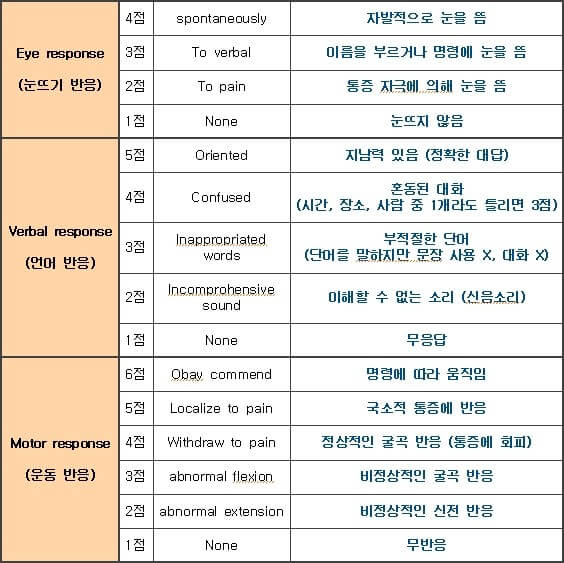

GCS란 의식장애의 중증도를 평가하기 위해 가장 흔히 사용되는 도구로, 눈뜨기 반응, 언어 반응, 운동 반응 세가지로 구성되어 있다. 항목마다 여러번 평가를 실시하며, 가장 좋은 반응을 기록한다.